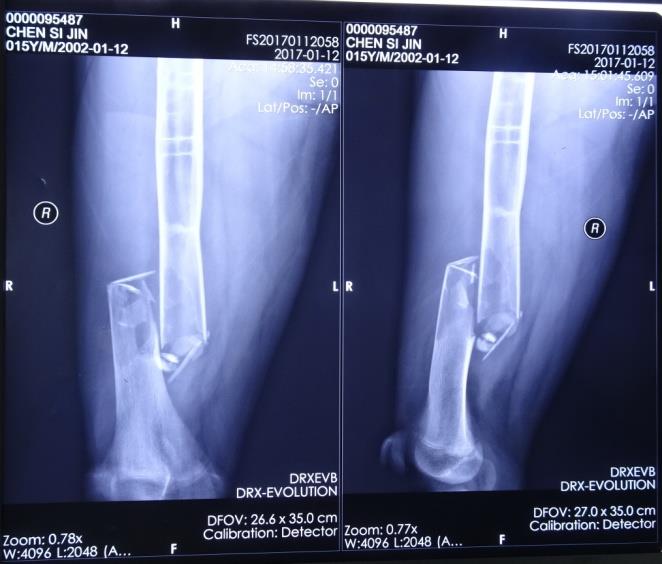

复阅十堰X医院2017年1月12日X线片(片号:FS20170112058)示:右股骨中下段骨折,右股骨中上段见横行短条状致密影,髓腔内见多发囊状低密度区,右股骨干膨胀不明显。

右股骨中下段骨折